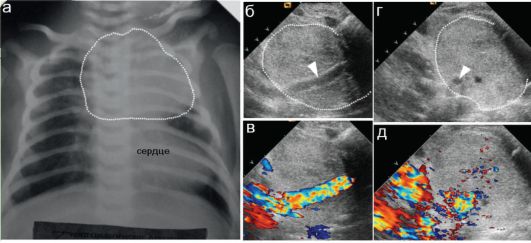

Тимомегалия: что это такое и как проявляется

Раздел: Фотоальбом решений